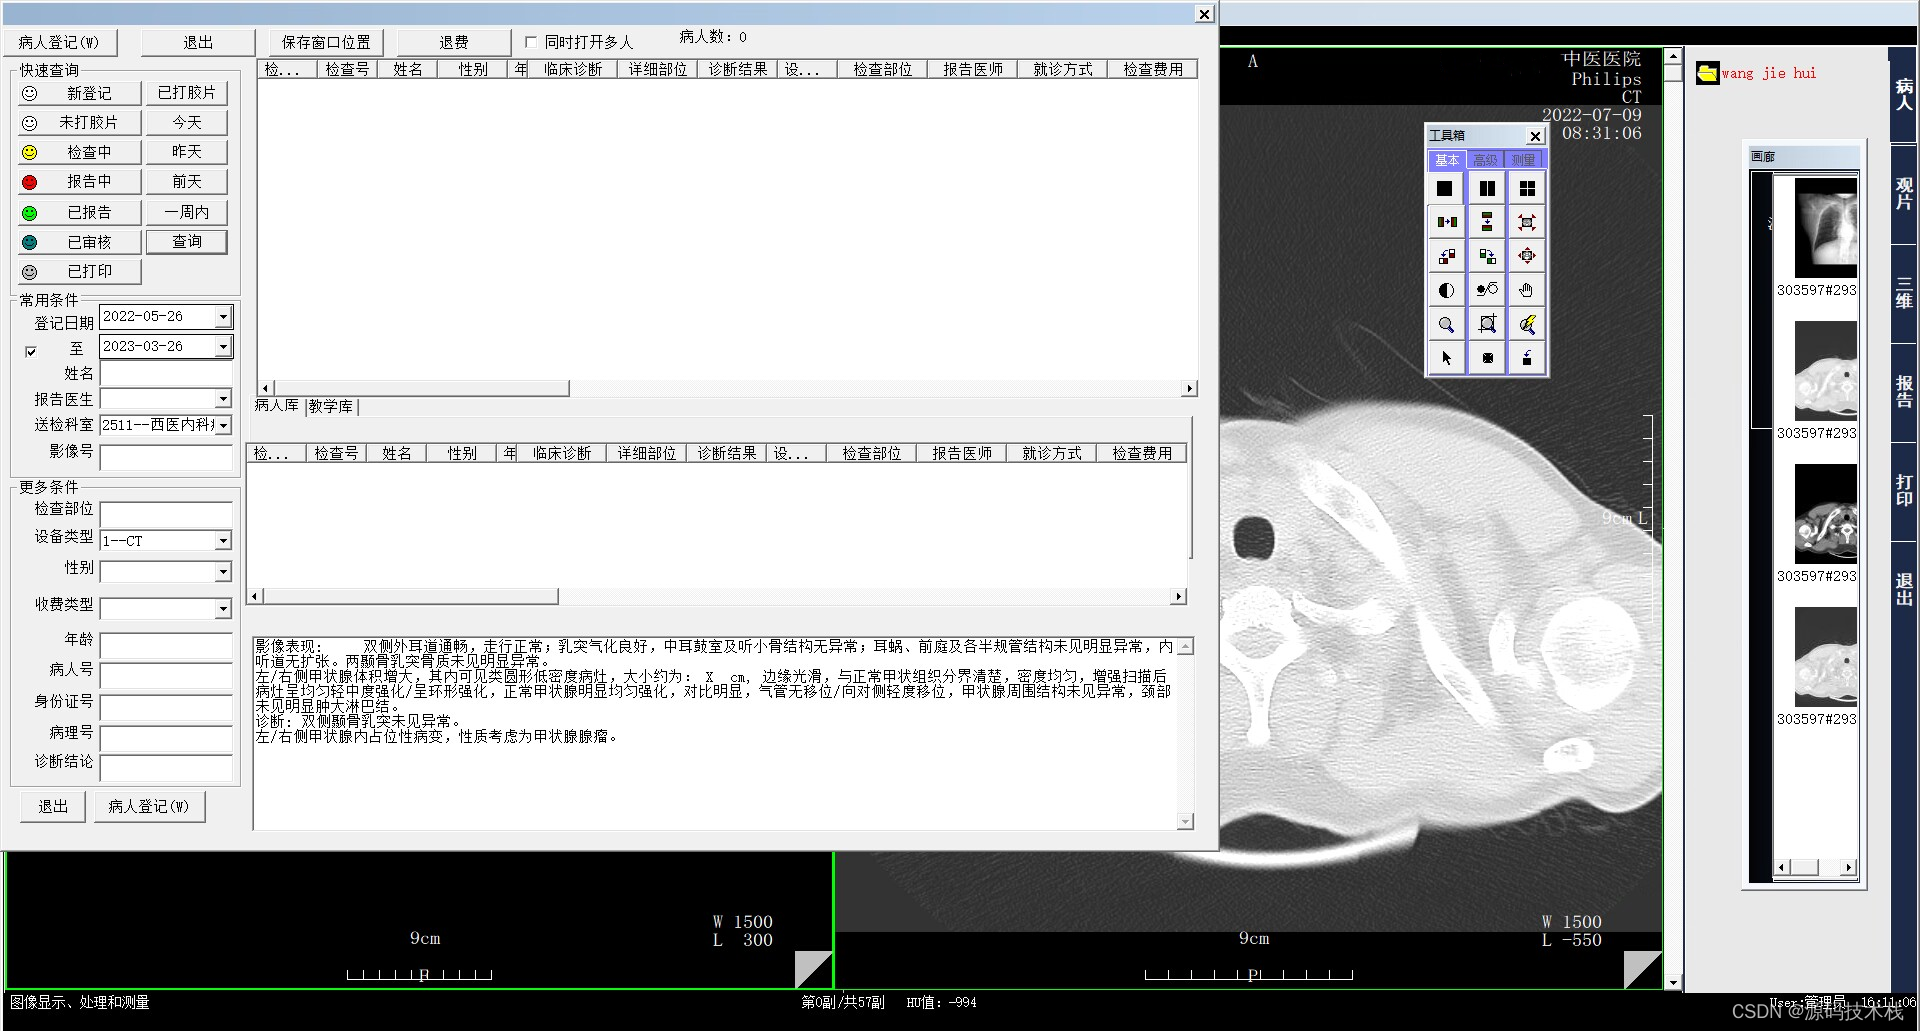

二、系统可实现检查预约、病人信息登记、计算机阅片、影像处理、电子报告书写、胶片打印、数据备份等一系列满足影像科室日常工作的功能。它以灵活的适应性和强大的扩展性为基础,以高效稳定为核心优势,充分结合国内外医学影像技术的发展趋势,遵循DICOM3.0,IHE,HL7等为国际标准开发而成。

1.覆盖登记、分诊、记费、报告生成和分发等内容,与RIS 有机结合;

9.病人报告历史记录管理,可显示同一病人所有检查记录;

11.可根据患者姓名、门诊/住院号、检查设备、检查部位、影像号、检查日期时间等组合查询,方便医生针对多种条件下获得影像资料的工作;